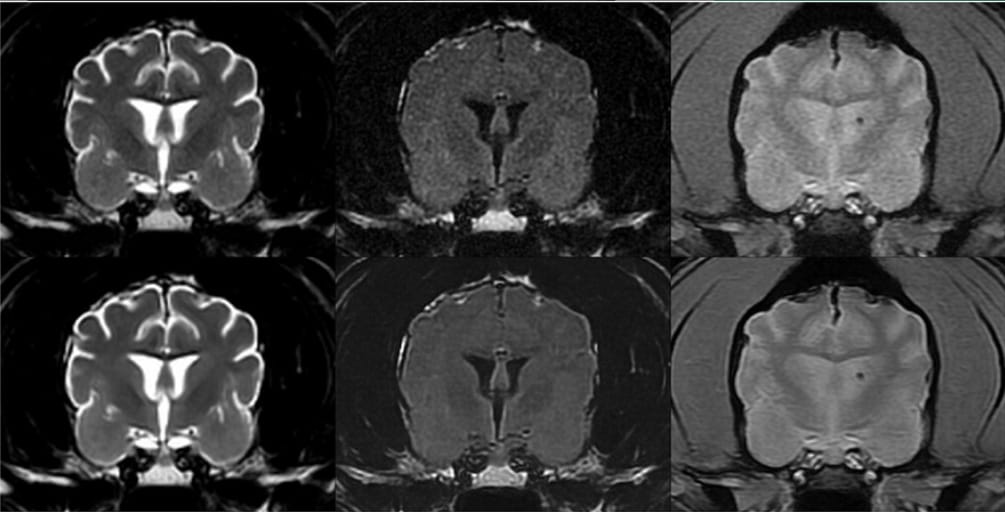

Transverse T2W (left), T2-FLAIR (middle), and GRE (right) brain MRI images in a 13-year-old standard poodle. Native images are at the top, and corresponding AI-treated images are at the bottom. For this patient, the increase in SNR on AI-treated images ranged between 77% and 109% for the T2W images, 24.6% and 37.3% for the T2-FLAIR images, and 61.9% and 84.7% for the GRE images. This patient received higher (i.e., better) coarseness, contrast, and overall quality scores for the AI-treated images than the native images. A left-sided microbleed is visible on the GRE images. Slice thickness = 3 mm, interslice gap = 0.5 mm, FOV = 14 cm; T2W image parameters: TR = 3665 ms, TE = 100 ms, NEX = 3; T2-FLAIR image parameters: TR = 8962 ms, TE = 146 ms, TI = 2376 ms, NEX = 2; GRE image parameters: TR = 717 ms, TE = 15 ms, Flip angle = 20°, NEX = 2.